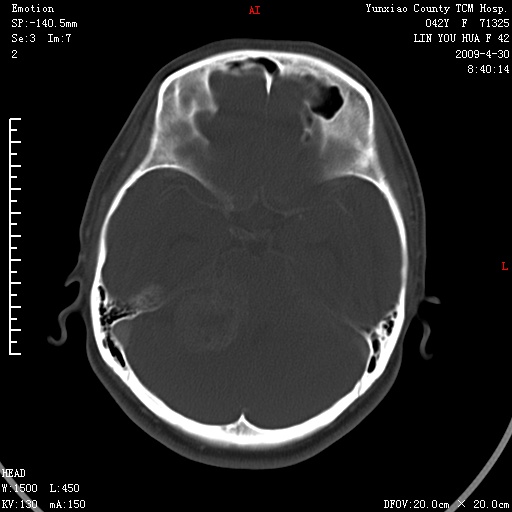

右侧桥小脑角区肿瘤,高密度囊变有显著强化,骨窗见内听道显著扩大,考虑听神经瘤可能性大

1)右侧听神经瘤。2)阻塞性脑积水。

内听道扩大,支持考虑听神经瘤可能性大。